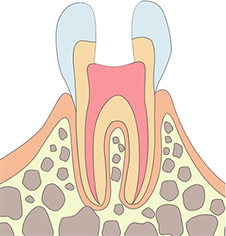

신경치료 과정

단계별 치료 과정을 통해 자연치아를 보존합니다

치수강개방

치수제거

치근관형성

치근관충전

크라운치료